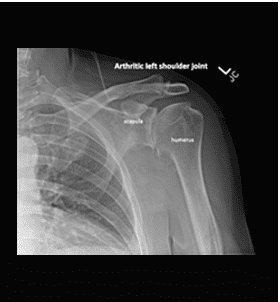

If you are suffering from shoulder or knee arthritis in Los Angeles and would like to explore your treatment options, sign up for a consultation today with the best Beverly Hills osteoarthritis doctor by calling (310) 595-1030.